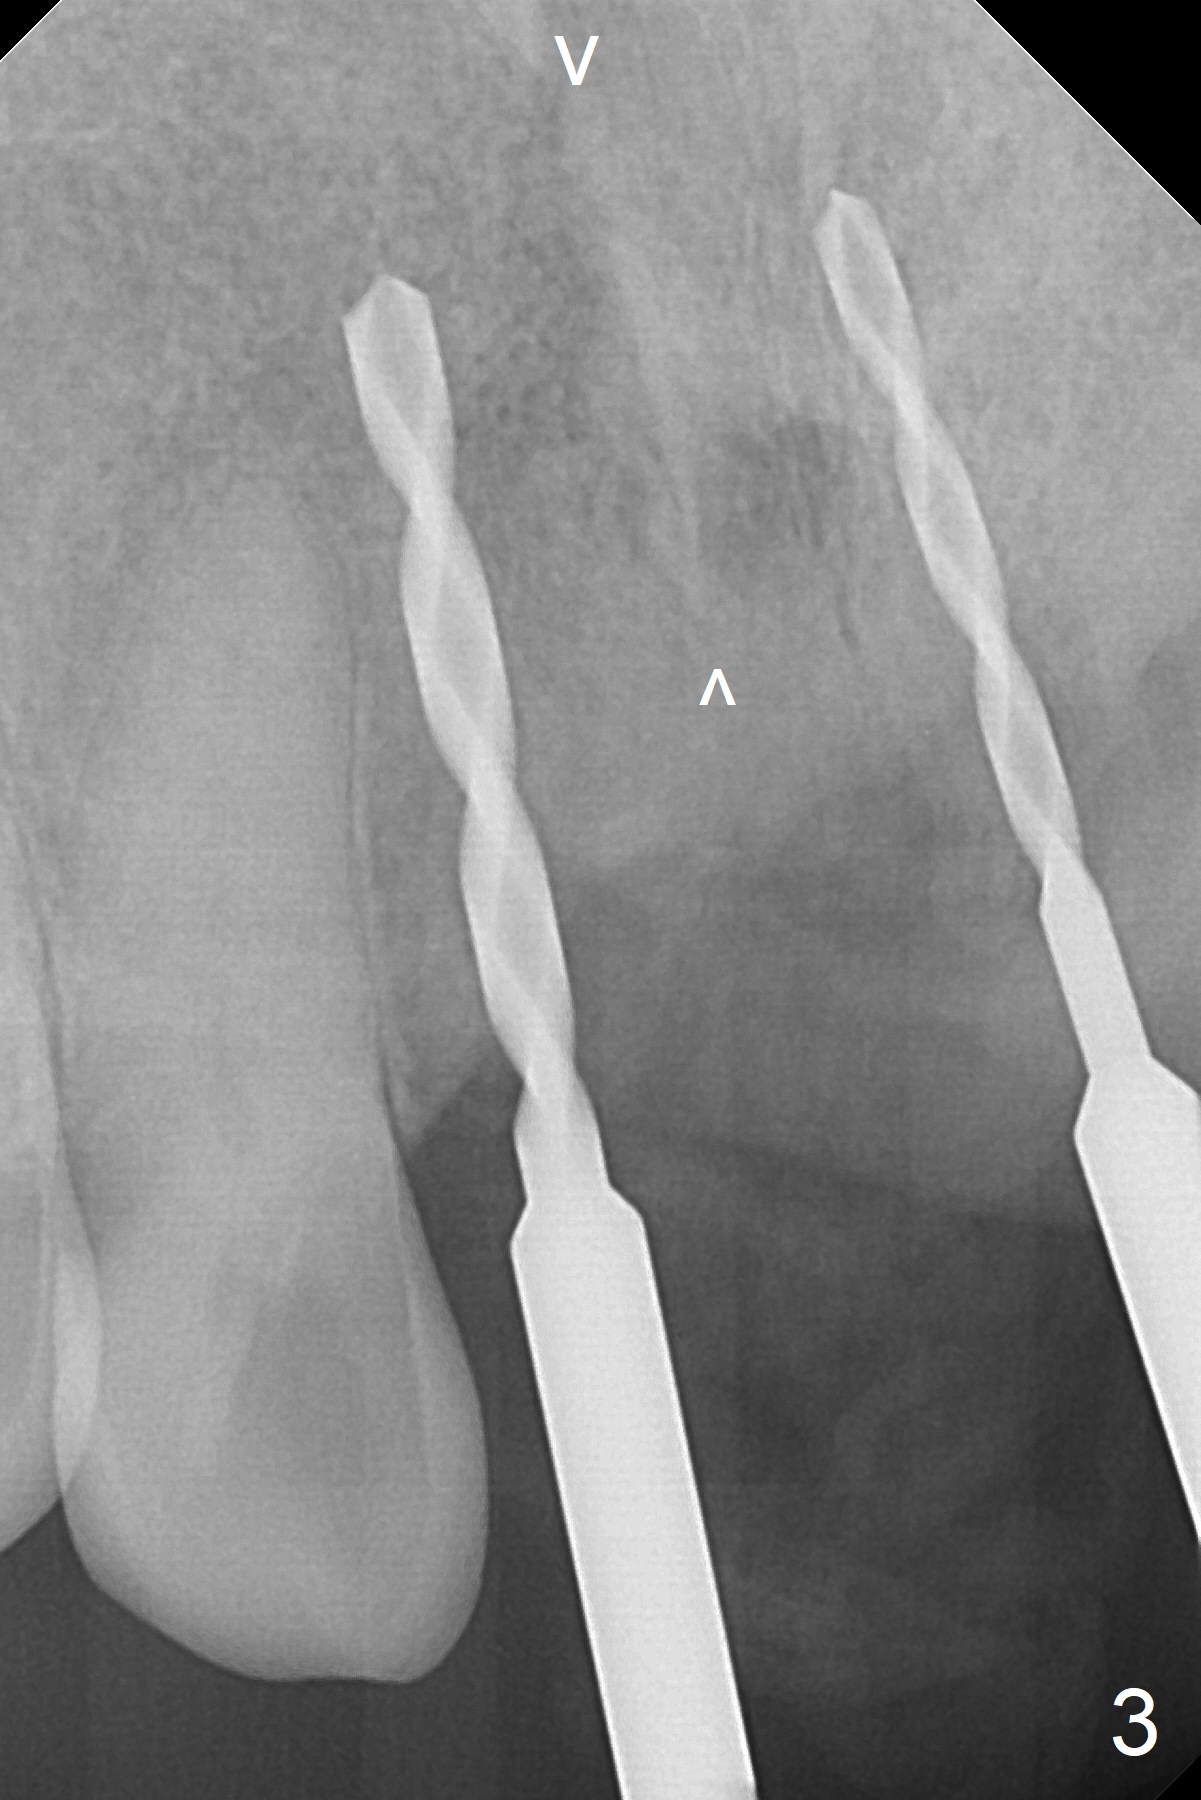

For implant placement of the atrophic ridge (Fig.1), osteotomy starts at #8 and 9 (Fig.2). Change in trajectory at #8 seems acceptable (Fig.3 (arrowheads: upper midline suture)). But it relapses when a 2x14(2) mm implant is placed (Fig.4 (2x14(4) mm at #9)). It appears that a drastic change in trajectory is necessary (Fig.5). In fact it is difficult to change the trajectory with the flexible 1.2 mm drill. Lindamann bur can be used for this purpose initially (coronally). The osteotomy should be moved mesially prior to reuse of the 1.2 mm drill for depth.